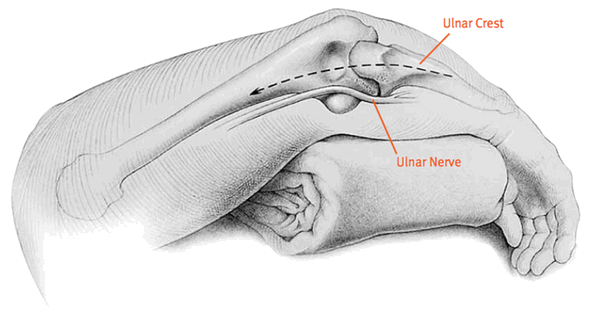

Эндопротезирование проводится под эндотрахеальным наркозом. Больной находится в горизонтальном положении лицом вниз. Конечность с пораженным суставом отведена в сторону. На руку между плечом и локтем накладывается жгут, чтобы снизить потери крови. Разрез выполняется по задней поверхности сустава. Нерв отделяется и закрепляется с помощью держателя. Сухожилия и фасции рассекаются.

Вставное соединение крепится бесцементной и цементной фиксацией. Локтевой нерв закрывается от металлической конструкции и фиксируется в отдельном канале. Это необходимо для избежания его травмирования. При зашивании на поверхность выводится дренажная трубка. После окончания операции рука больного разгибается и накладывается мягкая удерживающая повязка. В таком положении пациент должен пребывать не менее пяти дней.

Она проводится при туннельном синдроме. Заболевание развивается вследствие увеличенного давления на нерв, проходящий через локтевое сочленение. Зачастую оно возникает после ушибов и ощущается практически моментально: боль отдается в предплечье и кисть, появляется онемение на внутренней стороне конечности и на пальцах. Боль усиливается при сгибание локтя.

Данная процедура подразумевает перемещение нерва на переднюю часть стыка. Это позволит избежать натяжения нерва и возникновению боли. Для выполнения производится надрез в области надмыщелка, нерв извлекается из суставного канала и прокладывается по передней стороне сочленения. Такие операции проводятся крайне редко и только в ситуациях, когда устранить недуг нетравматическими способами невозможно.